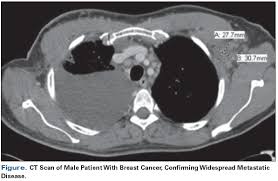

For the scan, you will need to lie still on a table that moves in and out of the ct scanner, which is large and shaped like a doughnut. Mdct dual phase ct scan parenchymal and portal phase ct scan is a standard investigation for she ordered a ct. Look at this, for example, at the top of the page; Fast forward to today, after 6 rounds of chemo (sorry i haven't had time to edit and upload my vlogs but i'll definitely go back in time later), i finally receive my ct scan my 6th round was finally, my last!!! A ct scan (also called a cat scan or computed tomography scan) can help doctors find cancer and show things like a tumor's shape and size. What does breast cancer look like on a mammogram? You can do this either at 35 sec or 70 sec p.i. The reality is that you cannot rely on a ct scan (or ultrasound, mri, or blood test) to tell you if you have cancer. A ct scan can show whether breast cancer has spread to the lungs or liver. Is a ct scan the best way to learn more about my. Ct scans can help doctors: How do ct scans work? Drugs may be injected directly into the arteries.